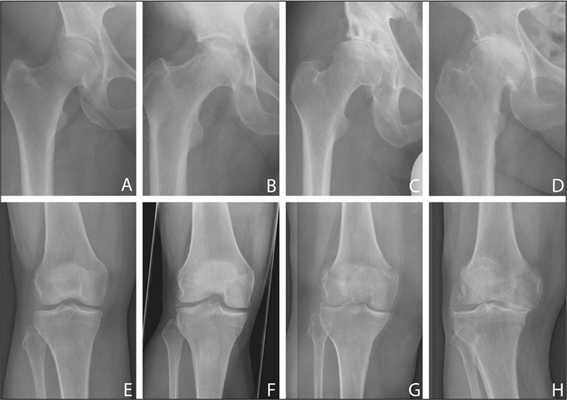

Для каждой стадии характерна своя симптоматика, выраженность которой зависит от степени сужения суставной щели, количества образовавшихся костных наростов.

| Степень тяжести коксартроза | Характерные симптомы и рентгенографические признаки |

| Первая | Суставная щель сужена неравномерно, вокруг вертлужной впадины сформировались единичные остеофиты. Возникают слабые дискомфортные ощущения, но чаще заболевание клинически не проявляется |

| Вторая | Суставная щель сужена почти в 2 раза, головка бедренной кости смещена, деформирована, увеличена, а костные наросты обнаруживаются даже за пределами хрящевой губы. Боли в бедре становятся постоянными, сопровождаются значительным ограничением подвижности |

| Третья | Полное или частичное сращение суставной щели, множественные костные разрастания, расширение головки бедренной кости. Боли возникают днем и ночью, распространяются на бедра, голени. Передвижение возможно только с помощью трости или костылей |

Рентгенологическое исследование

Стадия коксартроза устанавливается проведением рентгенографического исследования. На полученных изображениях отчетливо просматриваются деструктивные изменения в тазобедренном суставе. Это сужение суставной щели, деформация костных поверхностей, формирование остеофитов.